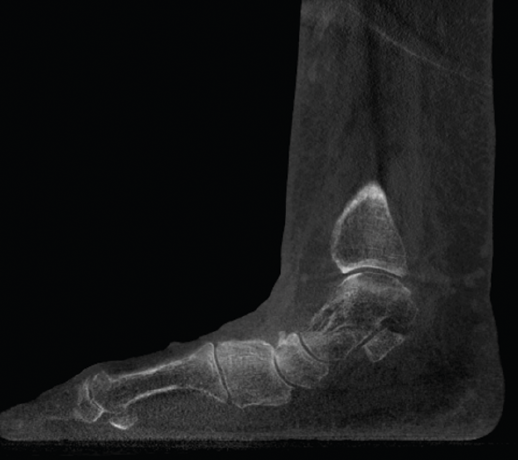

Figura 3. Inestabilidad franca de la columna medial en pie plano.

- Pie plano valgo del adulto. Permite la valoración de la articulación subtalar, el valgo del retropié y la inestabilidad de la columna medial (Figuras 2 y 3).